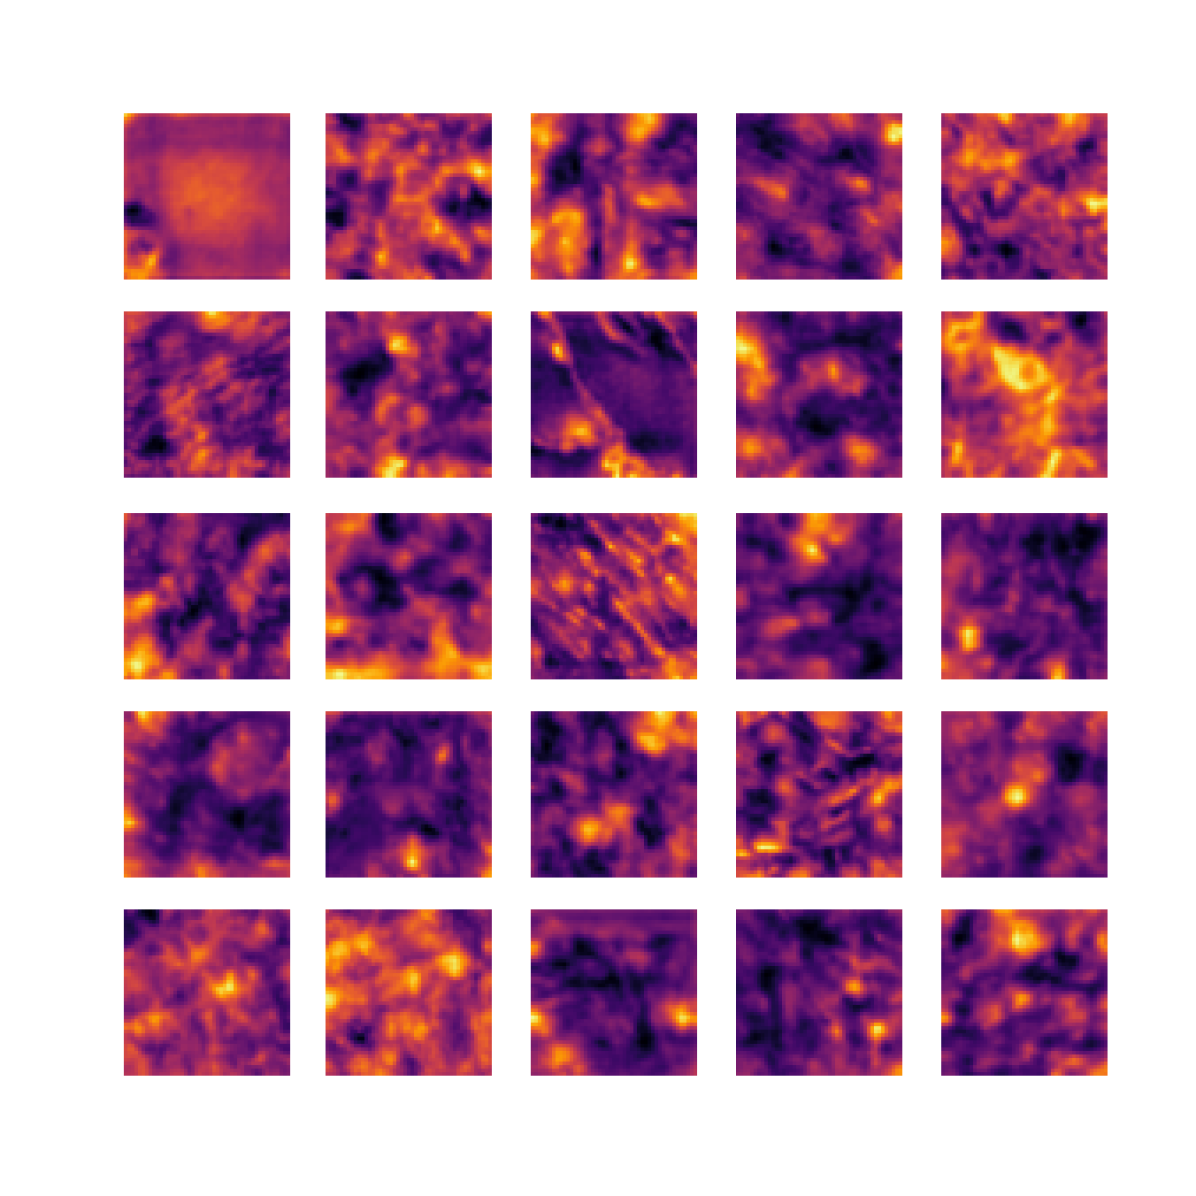

We also analyse the activation maps for each model using GradCAM as described in section S3. This offers more insight into the areas of the image which are contributing most heavily to the models’ representations. In Figure 4(b) we present some representative examples, however, a larger selection which was chosen at random is presented in Figures S10 to S25. The larger selection makes it easier to see the emergent patterns, including that privileged Siamese models tend to mainly identify features which are strongly present in both inputs, while unprivileged Siamese models tend to learn more diffuse features that are not specific to one cell phenotype or image region. TriDeNT ♆ incorporates both sets of features, learning both features specific to the privileged data and more the general features associated with unprivileged Siamese networks.

We can see in Figure 4(b) panel A that for ERG, the privileged Siamese model focuses almost exclusively on any nuclei which could be endothelial cells. As there are very few endothelial cells in the dataset, it could be an effective strategy to identify anything that could potentially be an endothelial cell to minimise the difference between the representations of the H&E model and the IF mask model. In the corresponding unprivileged Siamese image, we see that the model identifies some of these nuclei, albeit less strongly, but also focuses heavily on the other tissue and even the background, while strongly fixating on two spots of debris in the center of the image. This model has less ‘incentive’ to learn the weak features related to endothelial cells as these occur rarely and are not easy to detect, while more generic strong features such as the presence of connective tissue and the prevalence of background are more common and predictable from augmented images. We see that TriDeNT ♆ combines these two feature sets, strongly identifying nuclei while also identifying the connective tissue.

In panel C we see a similar pattern, with the privileged Siamese model fixating solely on the nuclei, while the TriDeNT ♆ model takes a more balanced approach. The unprivileged Siamese model appears to focus on a single cluster of nuclei while neglecting others, and similarly identifies an area of fibroblasts with its distinctive pattern but does not others.

In contrast to panels A and C which represent models with poor privileged Siamese results, panels B and D represent models whose privileged Siamese results were comparable to both TriDeNT ♆ and even the supervised baseline. It is therefore interesting to note that there are far more similarities between the privileged Siamese and TriDeNT ♆ models in both cases. Particularly in panel B, TriDeNT ♆ and the privileged Siamese model return virtually identical heatmaps, with both strongly identifying epithelial nuclei and neglecting the same areas of connective tissue. The unprivileged model in this case appears to focus solely on the centre of the image, giving a significantly different heatmap to the other panels.

Panel D again shows the previous pattern, with the privileged Siamese model identifying the features strongly present in the privileged data – fibroblasts – while neglecting the nuclei present. TriDeNT ♆ also strongly identifies the connective tissue, but, unlike the privileged Siamese model, does not completely neglect the nuclei. The unprivileged Siamese model primarily identifies background, and does not appear to identify the nuclei in this example.